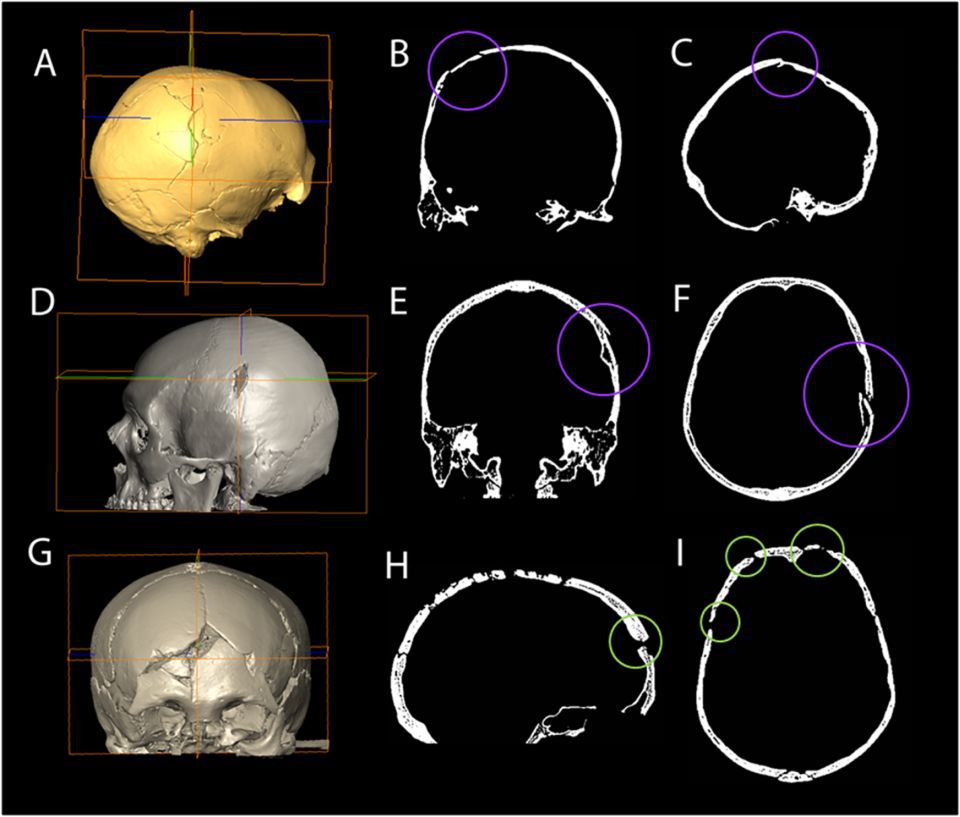

Craniul Cioclovina 1 / Credit foto: Elena F Kranioti Dan Grigorescu Katerina Harvat / Plos ONE

În cercetarea din prezent, specialiştii au reevaluat traumatismul craniului, în special o fractură mare din partea dreaptă, care a produs multe controverse în trecut, pentru a stabil dacă această leziune specifică a apărut la momentul decesului sau a fost un eveniment post-mortem.

Concluzia experimentului a fost că au existat două leziuni înainte sau chiar în momentul morţii: o fractură lineară la baza craniului, urmată de o alta în partea dreaptă a boltei craniene. Simulările au arătat că ambele fracturi au fost rezultatul unei lovituri consecutive cu o bâtă. Analiza cercetătorilor a indicat că ambele leziuni nu au fost rezultatul unei răniri accidentale, a unui eveniment post-mortem sau ca urmare a propriei căderi.

Credit foto: Elena F Kranioti Dan Grigorescu Katerina Harvat / Plos ONE